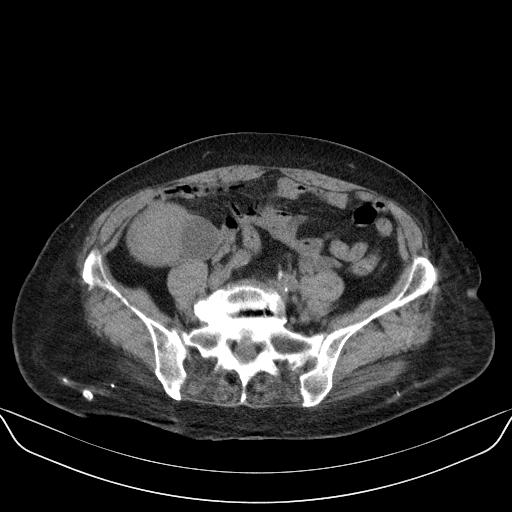

以下是引用yuhongjun在2010-3-12 6:32:00的发言:[br]回肠末端间质瘤,不除外阑尾粘液囊腺瘤,臀部注射性肉芽肿钙化. [br] [br]